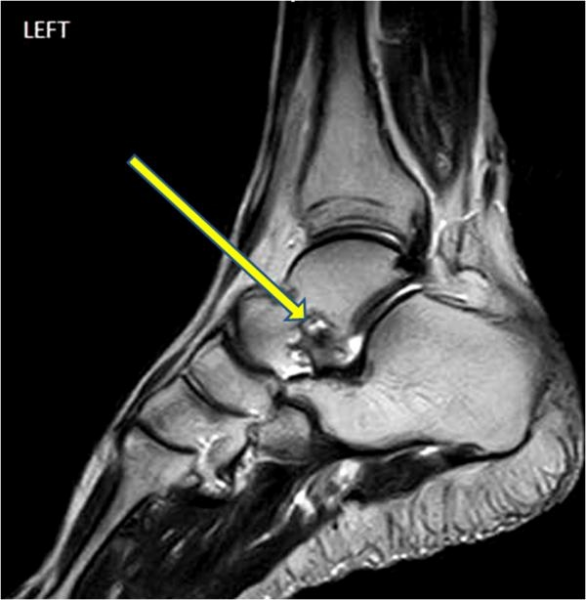

내측에 위치한 삼각인대가 매우 강하며 흔하지 않게 파열된다. 인대 파열보다는 외전 손상으로 대개 내측과의 견열 골절이 나타난다. 삼각인대는 네 개의 인대로 구성되는데, 표층에 둘, 심층에 둘로 이뤄져있다.

△ Medial Collateral (Deltoid) Ligament

(이미지 출처 : http://www.unmc.edu/dissection/idg35ankle.cfm)